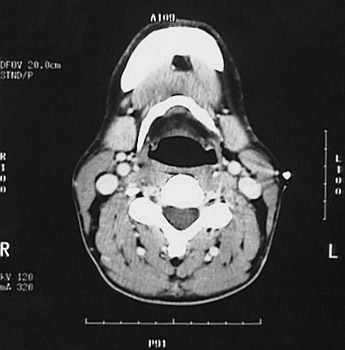

This is a normal axial head and neck CT scan demonstrating the mandible and pharynx and hyoid bone and submandibular gland and C4 and spinal canal and internal jugular vein and internal carotid artery and external carotid artery and trapezius muscle and splenius capitis muscle and sternocleidomastoid muscle.